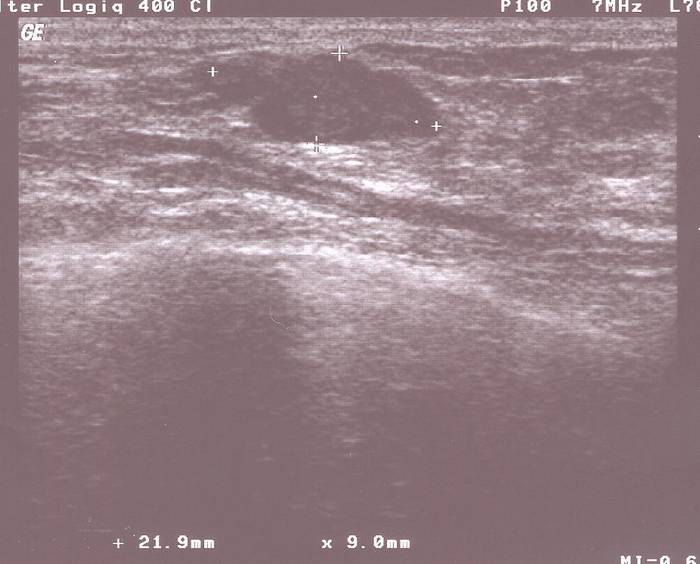

Fibroadenom von 22 x 9 mm Größe   Punktion: die Nadel kommt von rechts oben

Zum praktischen Vorgehen: Der Befund muss im Ultraschall sichtbar sein: Dann wird eine lokale Betäubung der Haut und des Gewebes bis zum Tumor vorgenommen und dann unter Ultraschallsicht punktiert.